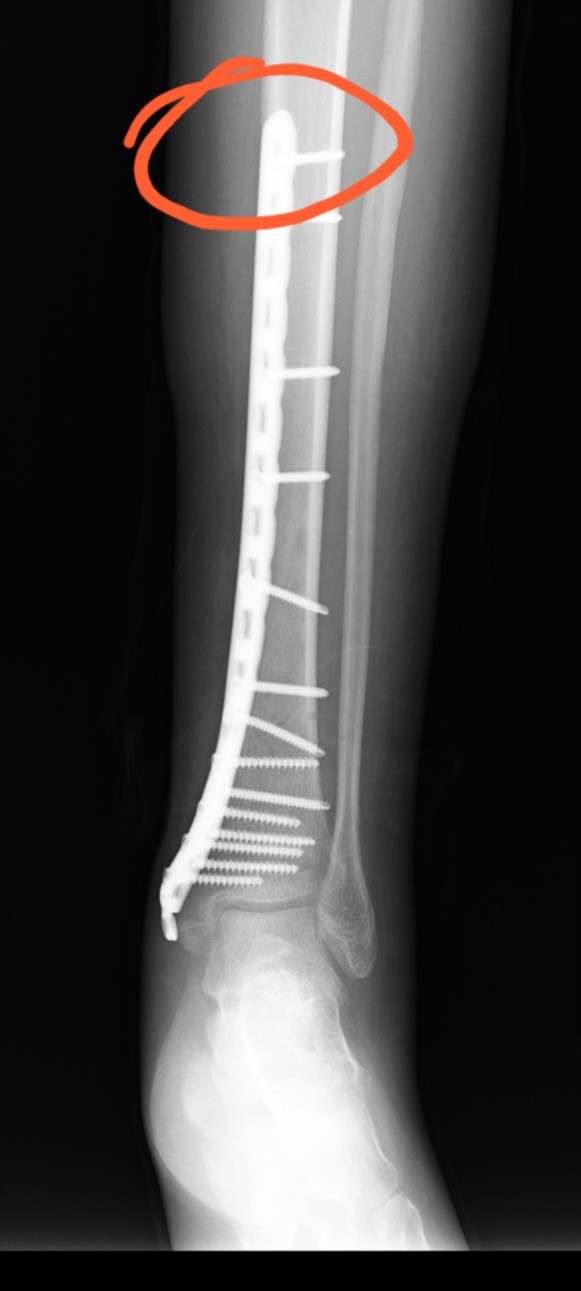

eskiden bendim şu anda da 1 vidam var gerçi, 1 hafta önce çıkardılar ameliyat ile ama 14 tane vida olunca bir tanesi kırılıp içeride kaldı, bilek kısmında idi sanırım öyle demişlerdi. bakalım o sorun çıkaracak gibi durmuyor lakin şu an eskiden plak olan (plağın üst kısmının ucu) yerdeki dokular iyileşme sürecine girdi herhalde.

şurası

garip bir sızı ve ağrı karışımı bir hissi var.

tam bu bölge yüksekten inerken kendini hissetiriyordu, bilek kısmındakiler rahatsız etmiyordu zaten, en üstü ediyordu genelde.bakalım dikişler çıkıp yürüyünce inşallah çıkmış diyeceğim umarım.